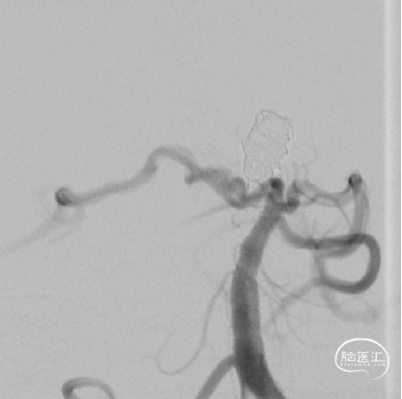

DSA:右侧P1段一6.8*9.7mm不规则囊状突起动脉瘤,远端P2段呈螺旋状蛇形动脉瘤改变。

DSA:右侧P1段一6.8*9.7mm不规则囊状突起动脉瘤,右侧A1段动脉瘤。夹层蛇形动脉瘤。

椎动脉压颈3D